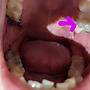

[問題] 疑似牙髓炎(國外.有圖慎入)

[ teeth_salon ]1 留言, 推噓總分: +1

作者: b120520 - 發表於 2020/10/15 15:43(5年前)